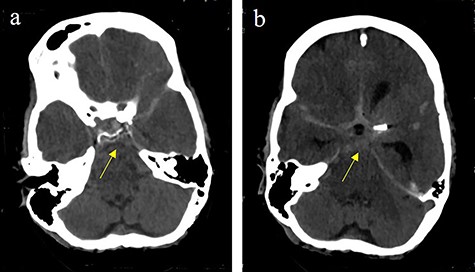

Subarachnoidal bleeding into the basal cistern-axial cranial computed tomography (cCT) at the level of (a) prepontine cistern (arrow) and (b) pentagonal cistern.

On the next day (Day 9 post-op), the patient suffered from acute and devastating headaches, with screaming and enuresis. An emergency computed tomography (CT) was carried out and displayed a prepontine and retroclival subarachnoid hemorrhage (Hunt & Hess Grade I), (Fig. 2). For further evaluation, a digital subtraction angiography (DSA) was conducted, and it showed a pseudoaneurysm of ophthalmic1/supraclinoid2/C23 part of the left ICA, which was directly treated by a flow diverter (Derivo®—4,5/20), with remaining rest flow (Fig. 3). The patient was transferred to the ICU, transcranial doppler sonography was performed and revealed normal flow. In the following course, the patient suffered from Terson’s syndrome and hyponatremia due to SIADH, but after clinical improvement, was transferred back to normal station after 10 days of post-operative monitoring. Furthermore, the patient was plagued with cephalgia and nausea, which could not be compensated with analgetics and antiemetics. On the 20th post-operative day after the epileptic seizure with postictal vigilance reduction, an emergency CTA was conducted showing progressive SAH (Fig. 4) and a growing pseudoaneurysm as well as generalized vasospasm with posthemorrhagic hydrocephalus. For an emergency CSF diversion, an external ventricle drain was placed. The repeated DSA showed a growing false aneurysm which was treated with two additional flow diverters (2× Derivo®—4,5/20) as well as coiling (HydroSoft™ 2/3 and 2× 1,5/2) by endoleak (Fig. 5). The vasospasms were treated by an intraarterial spasmolysis (Fig. 6).

Massive progress of SAH axial cCT at the level of (a) prepontine cistern (arrow) and (b) pentagonal cistern (arrow)